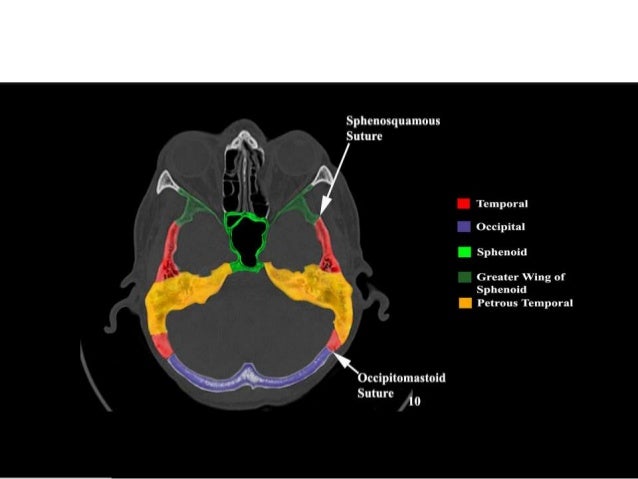

Ct skull base anatomy. You can however go directly to any section using the links below. B axial ct image with color coded overlay shows the skull base bones. The skull base can be evaluated by computed tomography ct which will demonstrate the bony structures of the skull base with its foramina and fissures for vessels and cranial nerves the temporal bone and sinonasal cavities.

Ct anatomy of skull base. Blue central skull base csb purple posterior skull base teal anterior skull base asb. Foramina of the skull base and the structures that pass through them.

Cranial foramina for further details. A axial three dimensional reconstructed ct image with color coded overlay shows the skull base sections. Ct anatomy of skull base.

Blue temporal bones fuchsia nasal bones green ethmoid bone light pink vomer purple occipital bones teal sphenoid bone yellow zygomatic bones. Basic anatomy review the bones sutures and fissures that comprise the skull base. Detailed anatomy enter this module for a more detailed review of skull base anatomy.

Ct is more sensitive in detecting fibro osseous skull base lesions calcification and sclerosis. The module interface is meant to mimic a radiology workstation with adjacent image scrolling via arrow keys and or mouse wheel button. Navigating the skull base identify the petro occipital fissure to navigate the major structures of the skull base.